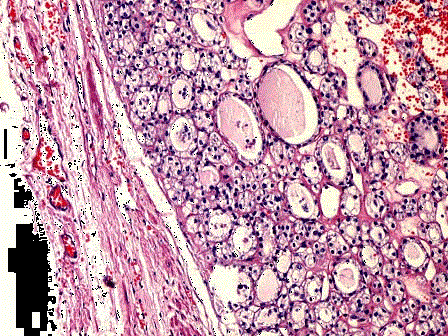

问题 如图为甲状腺腺瘤镜下观和甲状腺高分化滤泡癌镜下观,仔细比较,二者最重要的区别是 ( )

选项 A.是否具有完整包膜 B.高分化滤泡癌的滤泡结构和上皮细胞形态异型性明显 C.肿瘤包膜、血管受侵犯和发生转移才能确诊为癌 D.核分裂象的多少是诊断标准 E.患者年龄的大小是决定因素

答案 C